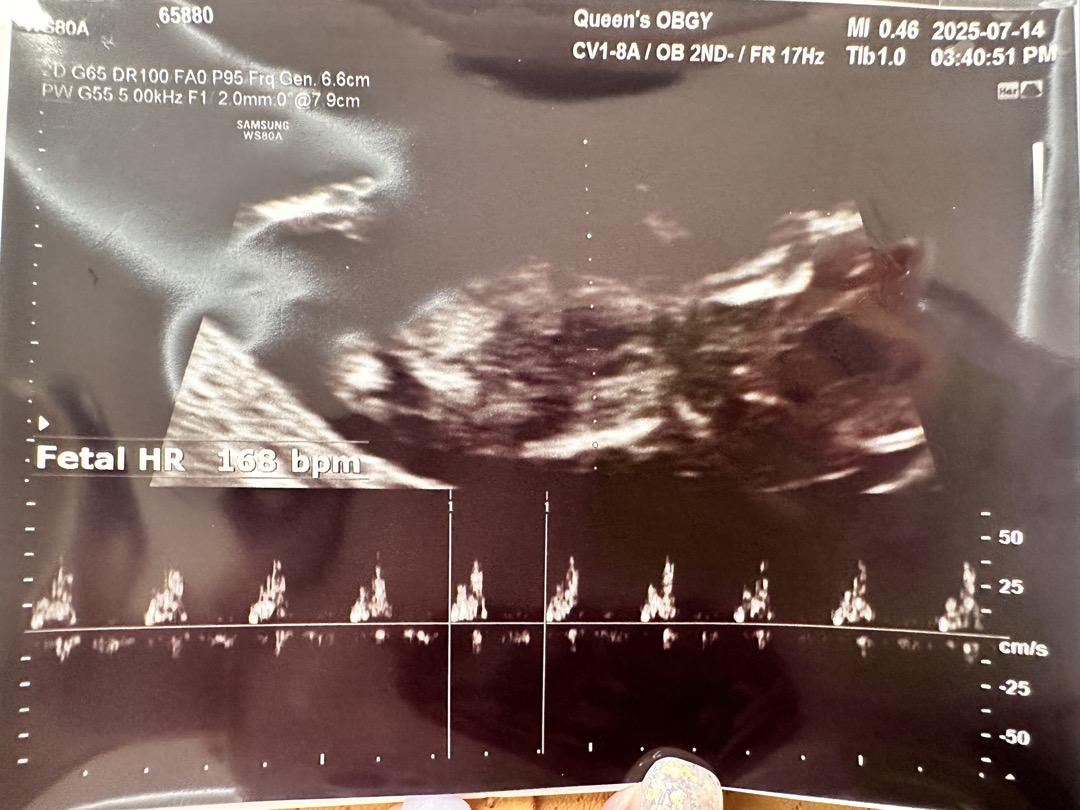

각도법좀 봐주세요 고수님들(__ )

13주라 아직 성별을 알수가 없는데 너무 궁금해요!!!